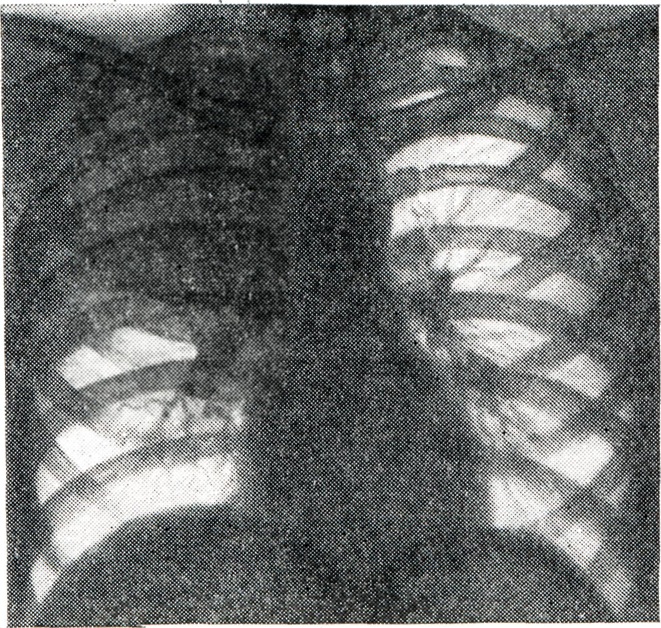

При максимальном спадении какой-нибудь доли почти вся полость грудной клетки на стороне ателектаза может быть заполнена только расширенными соседними долями. Небольшое уменьшение спавшейся части легкого может компенсироваться расширением соседних его отделов без изменений топографии органов грудной клетки. По Ван-Аллену (Van-Allen), для ателектаза характерна полная однородность тени, так называемый симптом матового стекла, который, однако, не патогномоничен для ателектаза, так как наблюдается также при циррозе легкого, иногда — при массивной острой пневмонии; в части случаев тень ателектаза представляется негомогенной из-за наложения изображения окружающей легочной ткани. Интенсивность тени ателектаза обычно велика, в особенности при больших его размерах, при значительной гиперемии и отечности спавшейся легочной ткани. Интенсивность затемнения зависит не только от плотности ателектаза, но и от степени вздутия (просветления) соседних отделов легкого. При значительном расширении последних тень ателектаза в силу известных закономерностей суммации теней обусловливает лишь картину понижения прозрачности легочного поля. Истинный характер затемнения может быть в этих условиях установлен только при исследовании грудной клетки в боковом положении (рис. 2). Выше и ниже затемнения легочное поле представляется в различной степени просветленным, более значительно в непосредственной окружности ателектаза. Соответственно растянутым отделам легкого обедняется легочный рисунок: промежутки между тенями сосудистых стволов увеличиваются, число мелких сосудистых теней уменьшается.

Рис. 2.

Ателектаз верхней доли левого легкого со смещением средостения влево при центральном раке левого легкого (рентгенограммы: а — прямая проекция; б — боковая проекция; выражено затемнение в области ателектаза).